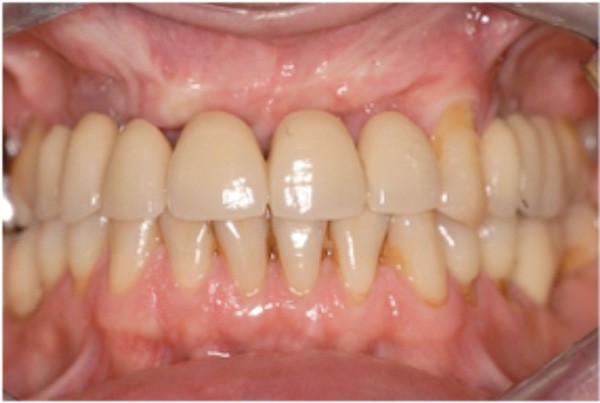

Cette partie de la présentation ne se contentait pas de rapporter les principes précédemment décrits à des régions limitées des maxillaires mais étendait la discussion à la difficulté majeure rencontrée en implantologie : rattraper des erreurs de positionnement implantaire ayant entraîné des compromis prothétiques inesthétiques. La solution thérapeutique mise en œuvre par Benoît Philippe consiste à appliquer la procédure d’ostéotomie segmentaire à l’entité constituée par l’os alvéolaire péri-implantaire et les implants. Les couronnes implantaires sont déposées. Le tracé d’ostéotomie encadre le segment à repositionner mais n’implique pas la corticale palatine qui sera fracturée pour éviter toute lésion du périoste (nourricier du segment alvéolo-implantaire). Un dispositif prothétique préparé en amont guide la translation du fragment qui est fixé au moyen de plaque d’ostéosynthèse dans la situation idéale. Le capital squelettique est reconstruit et l’espace prothétique disponible est normalisé.

Au cours de la conférence, Benoît Philippe a énoncé ses convictions concernant les conditions de succès du traitement implanto- prothétique : le respect d’une biomécanique implantaire équilibrée, le recours à des implants plus fins et moins nombreux que ne l’imposaient les préconisations d’autrefois, l’observation du biotype parodontal plus ou moins favorable aux reconstructions des atrophies étendues, la nécessité de restaurer au préalable puis de maintenir un environnement parodontal satisfaisant (en particulier la gencive attachée péri-implantaire).